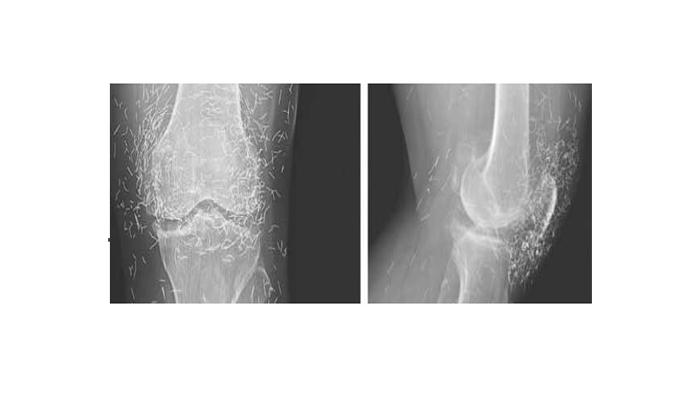

عندما فحص الأطباء صورة بالأشعة السينية لركبة امرأة تعاني من آلام حادة في المفاصل، عثروا على معدن من الذهب: مئات من إبر الوخز الصغيرة التي بقيت في أنسجتها.

‎ونقلت صحيفة "الاتحاد" الإماراتية عن موقع شبكة "فوكس نيوز": أن المرأة الكورية الجنوبية، البالغة من العمر 65 عاماً، كانت قد شخصت إصابتها بمرض هشاشة العظام، وهو مرض تتدهور معه الغضاريف والعظام الموجودة في المفاصل؛ ما يؤدي إلى الآلام والتصلب.

وقالت "التقارير": إنه في حالة المرأة؛ فإن الإبر التي يعتقد أنها من "الذهب"، تركت عمداً في أنسجة المريضة؛ لتواصل تحفيزها.

‎ويقول الدكتور علي قرمازي، أستاذ الأشعة في جامعة بوسطن: إن ترك أجسام غريبة في جسم الإنسان ليست فكرة جيدة؛ لأن ذلك قد يؤدي إلى التهابات وتعفنات، كما أنها قد تصعب على الطبيب قراءة صورة الأشعة بشكل صحيح.